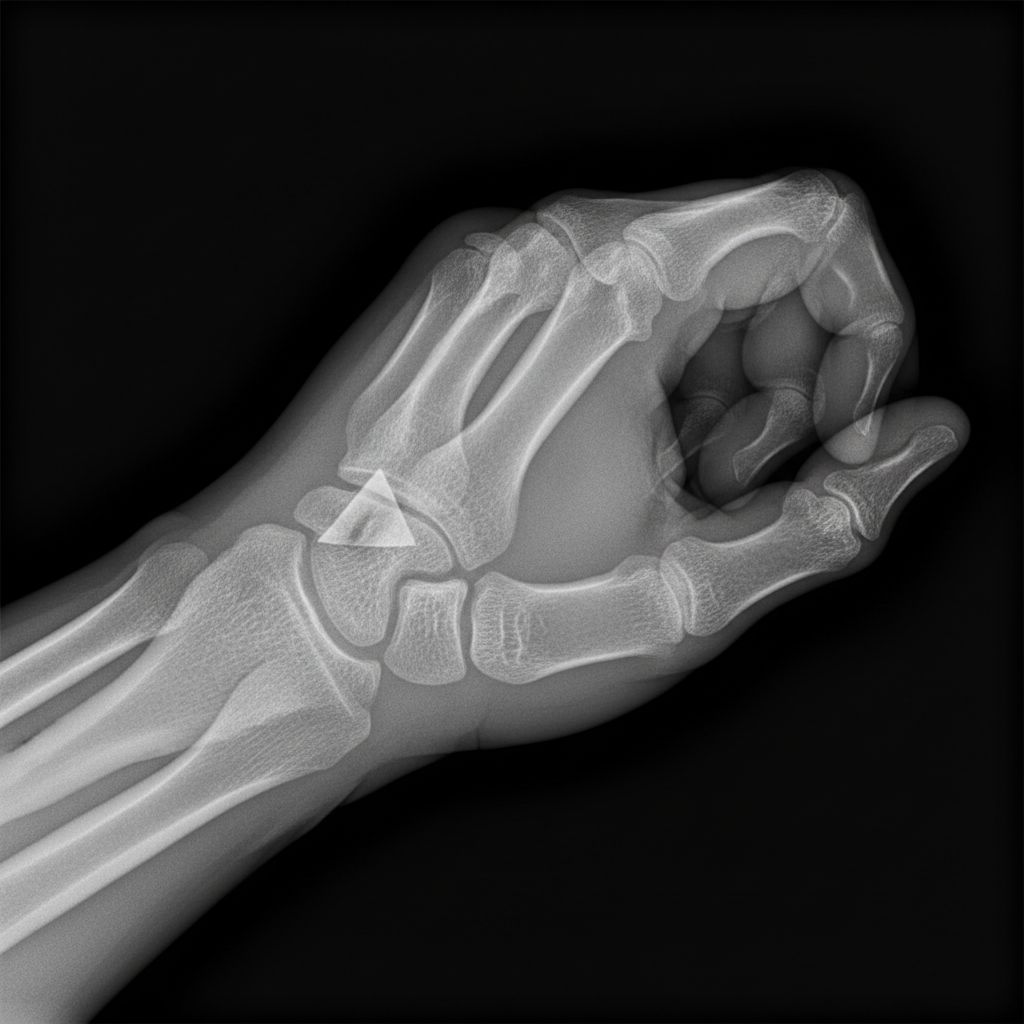

Fracture shown in this radiograph is:

Explanation: ***Bennett's fracture*** - This is a **fracture-dislocation** of the **base of the first metacarpal** involving the **carpometacarpal (CMC) joint** of the thumb. - The **abductor pollicis longus (APL)** pulls the metacarpal **proximally and radially**, causing characteristic displacement with a small **ulnar fragment** remaining attached to the trapezium. *Colles' fracture* - This involves the **distal radius** with **dorsal angulation** and typically occurs after a fall on an outstretched hand. - It does not involve the **thumb metacarpal** or **CMC joint**, making it anatomically distinct from the fracture shown. *Smith's fracture* - This is a **reverse Colles' fracture** of the **distal radius** with **volar angulation** of the distal fragment. - Like Colles', it affects the **forearm bones**, not the **thumb metacarpal** as seen in this radiograph. *Rolando's fracture* - This is a **comminuted fracture** of the **base of the first metacarpal** with **multiple fragments** involving the CMC joint. - Unlike Bennett's fracture, it shows **Y-shaped** or **T-shaped** fracture lines with **three or more fragments**, not the simple two-part fracture pattern shown.